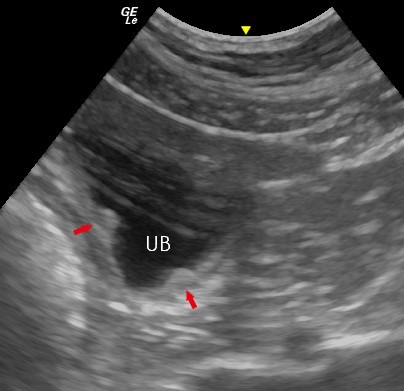

Figure 1. Normal Bladder Wall – In this sagittal plane image of the bladder, the layered appearance of the normal urinary bladder (UB) can be seen (between the arrows).

Although not visible in normal patients, the distal ureters should also be evaluated at the point where the intramural portion of the ureter enters the bladder. These small convex protuberances, the ureteral papillae, can often be visualised on the dorsal wall of the bladder neck at the bladder trigone (Figure 2). Urine enters the bladder from the ureters in peristaltic jets which may be seen as intermittent flows of echogenic fluid projected into the anechoic urine. This effect is caused by a difference in specific gravity between urine within the bladder lumen and urine entering from the ureter. This phenomenon can also be observed using colour doppler.

Figure 2. Normal Ureteral Papillae – In this transverse plane image of the bladder taken at the level of the bladder neck, the ureteric papillae (arrows) appear as small protuberances or ‘focal thickenings’ of the dorsal urinary bladder (UB) wall near the cranial aspect of the trigone.